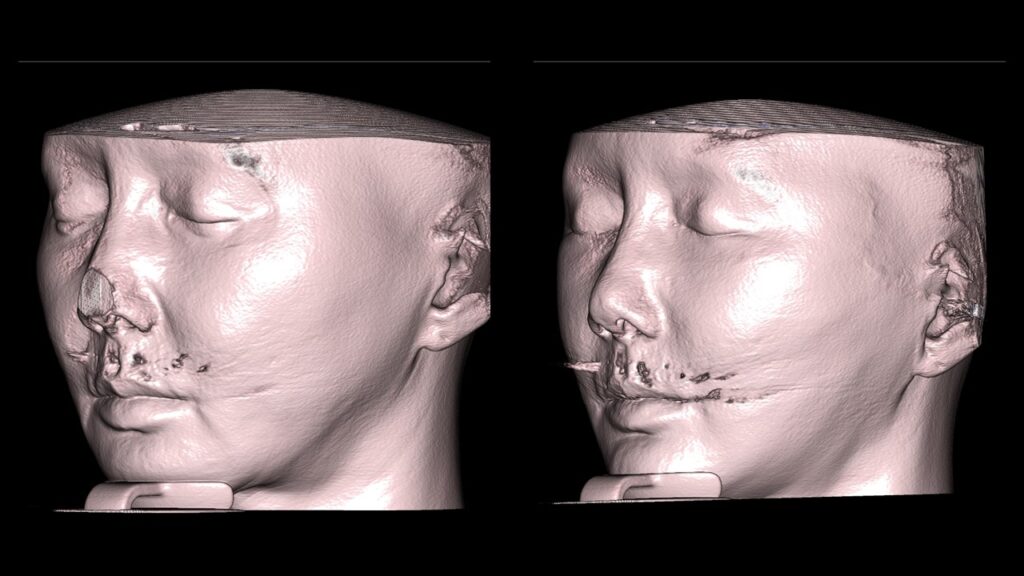

4. Case Studies (3DCT & Medical Photos)

-

Case 2: (Zygoma + Chin Advancement + Face Lift + Brow Lift) Dramatic improvement in the side profile and double chin within just 1 month.